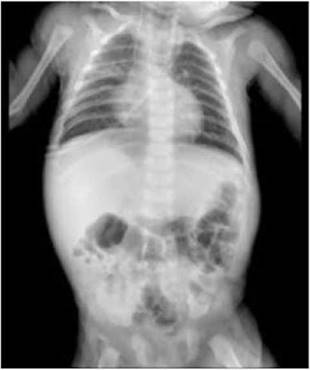

Se presenta un caso clínico de un lactante de 38 semanas de edad, procedente de la ciudad de Chiclayo en Perú, quien fue ingresado a la sala de emergencias del Hospital Regional Lambayeque por un cuadro febril y dificultad respiratoria, seis horas después de su ingreso, se acentuó el distrés respiratorio, lo que llevó a la intubación y conexión a ventilación mecánica invasiva. Tras la evaluación de los resultados de Radiografía (Figura 1) se inició el tratamiento antimicrobiano con Ceftriaxona y Azitromicina, junto con sedoanalgesia a base de Midazolam y Fentanilo.

Figura 1. Radiografía al ingreso del paciente al servicio de emergencia (día 1) que revela Campos pulmonares hiperinsuflados. Arcos costales horizontales. Imágenes hiliofugales. Consolidación basal derecha y cardiomegalia